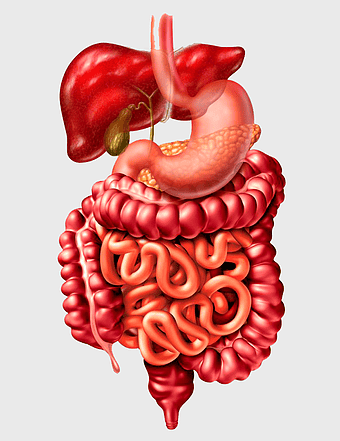

Gastrointestinal tract anatomy, Stomach health, Crohn's disease symptoms, Digestive system, Intestinal inflammation, Human anatomy illustration, Medical diagram -

digestive system diagram, gastrointestinal tract chart, human anatomy illustration, small intestine function, digestive process visualization, internal organ layout, metabolic system overview -

Gastrointestinal tract diagram, Small intestine anatomy, Large intestine function, Apparato digerente illustration, Digestive system structure, Intestinal health, Human anatomy organs -

Gastrointestinal tract illustration, leaky gut syndrome symptoms, small intestine diagram, large intestine function, digestive system health, human anatomy chart, internal organ visualization -